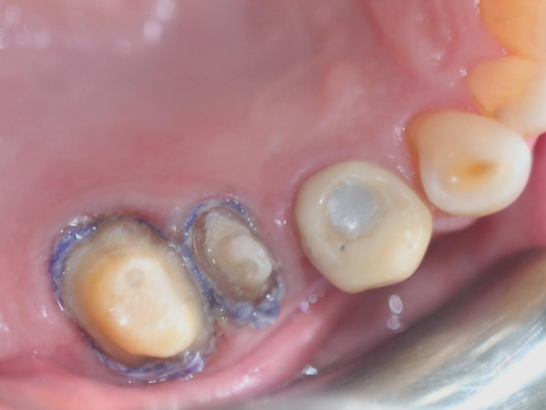

Case i

Step 4: Place the second retraction cord in the gingival sulcus

Choose a retraction cord that fills the gingival sulcus. It can be observed that the retraction cord completely surrounds the tooth. The second retraction cord often needs to be impregnated with hemostatic material.